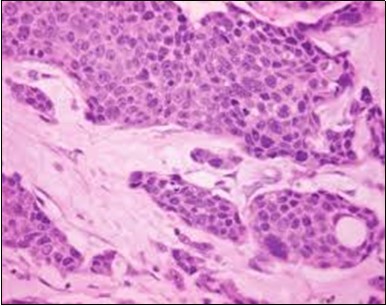

Granular arrangement of malignant cells and intercellular bridges are conspicuous with the demonstration of nuclear atypia, pleomorphism, prominent mitosis and tumour necrosis. A peripheral palisade is discernible within the cellular aggregates. Mitotic figures are common and can be quantified as up to 12 mitosis/ high power field. Tumour differentiation can prominently be of the ductal category with the demonstration of intra-cytoplasmic lumina. Comedo type tumour necrosis is evident along with foci of squamous differentiation The neoplasm is reactive to periodic acid Schiff ‘s (PAS) stain. (Figure 1, Figure 2, Figure 3, Figure 4, Figure 5, Figure 6, Figure 7, Figure 8, Figure 9, Figure 10, Figure 11, Figure 12, Figure 13.

Figure 2.Epidermal projections lined with atypical and malignant epithelial cells in eccrine porocarcinoma (14).

Figure 3.Cohesive accumulations with numerous ductular articulations of carcinoma cells in eccrine porocarcinoma (15).

Figure 9.Branches and cords of malignant epithelial cells in eccrine porocarcinoma with a superficial, abutting epithelium and mitotic figures(21).

Figure 10.Duct like configurations and atypical epithelial cells with prominent mitosis in eccrine porocarcinoma (22).